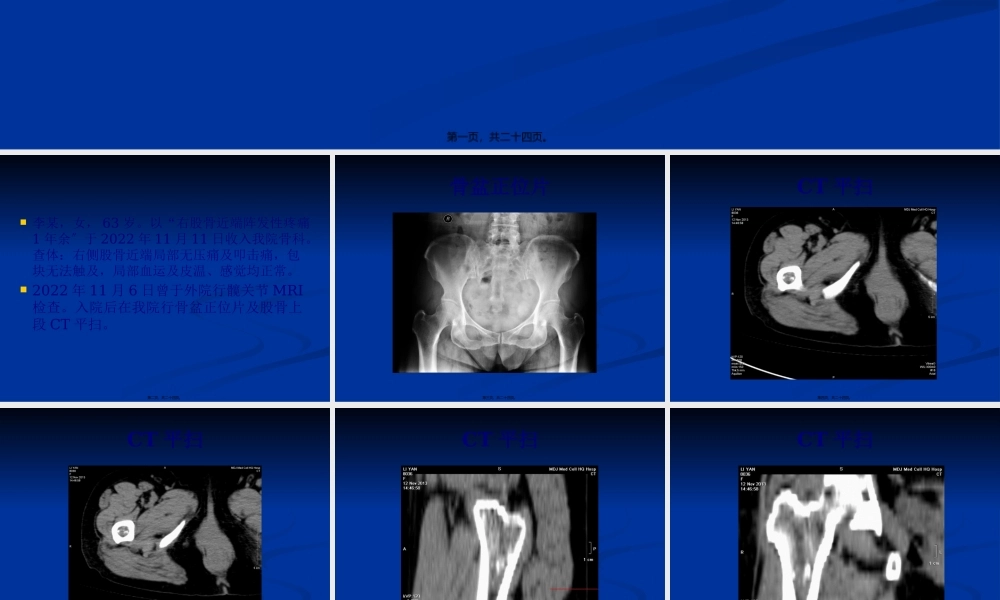

病例讨论第一页,共二十四页。李某,女,63岁。以“右股骨近端阵发性疼痛1年余〞于2022年11月11日收入我院骨科。查体:右侧股骨近端局部无压痛及叩击痛,包块无法触及,局部血运及皮温、感觉均正常。2022年11月6日曾于外院行髋关节MRI检查。入院后在我院行骨盆正位片及股骨上段CT平扫。第二页,共二十四页。骨盆正位片第三页,共二十四页。CT平扫第四页,共二十四页。CT平扫第五页,共二十四页。CT平扫第六页,共二十四页。CT平扫第七页,共二十四页。MRI第八页,共二十四页。MRI第九页,共二十四页。MRI压脂第十页,共二十四页。MRI压脂第十一页,共二十四页。MRI压脂第十二页,共二十四页。外院髋关节MRI发现右侧股骨近端肿物,考虑良性病变。患者于我院行手术治疗。第十三页,共二十四页。讨论第十四页,共二十四页。术后病理结果:符合内生性软骨瘤,局部软骨组织细胞增生活泼。请结合临床及影像学表现。第十五页,共二十四页。软骨瘤属于成软骨性肿瘤。软骨瘤是常见的骨良性肿瘤,据病灶数目可分为单发性软骨瘤和多发性软骨瘤,根据病变部位可分为内生性软骨瘤和外生性〔皮质旁〕软骨瘤。单发性软骨瘤多见于干骺端和骨干髓腔。多发性软骨瘤可发生在骨髓腔、骨皮质和骨膜,其中以髓腔〔内生性〕者多见。第十六页,共二十四页。临床与病理内生性软骨瘤多发生于11~30岁,其次为31~50岁。男性多见。常发生于手足短管状骨。主要病症是轻微疼痛及压痛,位于表浅者见局部肿块。肿块外表光滑,质硬,局部皮肤正常。可合并病理性骨折。镜下对软骨瘤和软骨肉瘤的鉴别,有时极困难,应密切结合临床和影像学表现。第十七页,共二十四页。X线表现病变位于骨干者多为中心性生长,而位于干骺端者那么以偏心性生长为主。内生性软骨瘤位于髓腔内,表现为边界清楚的类圆形骨质破坏区,多有硬化边与正常骨质相隔。病变邻近的骨皮质变薄或偏心性膨出,其内缘因骨脊而凹凸不平或呈多弧状。由于骨脊的投影,骨破坏区可呈多房样改变。骨破坏区内可见小环形、点状或不规那么钙化影,以中心部位多见。第十八页,共二十四页。X线表现与发生在短管状骨的内生性软骨瘤相比,长骨内生性软骨瘤膨胀常不明显,不侵蚀骨皮质内层,骨皮质无明显变薄,很少发生病理性骨折,无骨膜反响及软组织肿块。主要原因为长管状骨生长空间大。第十九页,共二十四页。CT表现可见髓腔内异常软组织密度影,密度略低于肌肉,其内可见小环形、点状或不规那么钙化影。...